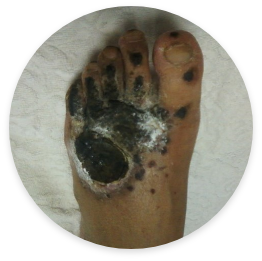

Stem Cell on Diabetic Foot Ulcer

줄기세포의 당뇨족 치료

당뇨 합병증인 족부궤양은 난치성 질환으로 패혈증 등의 합병증을 유발한다.

중증의 경우, 발가락이나 발목절단 등의 외과적 치료가 필요할 수 있으나 줄기세포 치료를 통하여 발의 기능을 보존할 수 있다.

아래는 줄기세포 시술로 인한 당뇨족의 변화과정이다.

• 줄기세포 시술 전

• 줄기세포 1차

투여 후

• 줄기세포 2차

• 줄기세포 5차